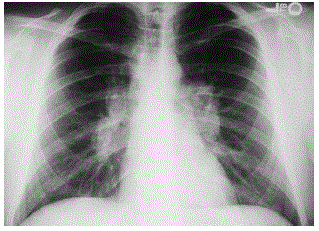

Um homem de 30 anos procurou atendimento médico devido à alteração de radiografia de tórax encontrada quando fez exames de rotina (figura abaixo). A princípio não relatava queixas, mas na anamnese dirigida referiu tosse seca há cerca de 6 meses. HPP: paralisia facial periférica há 3 meses com boa recuperação. O diagnóstico provável é